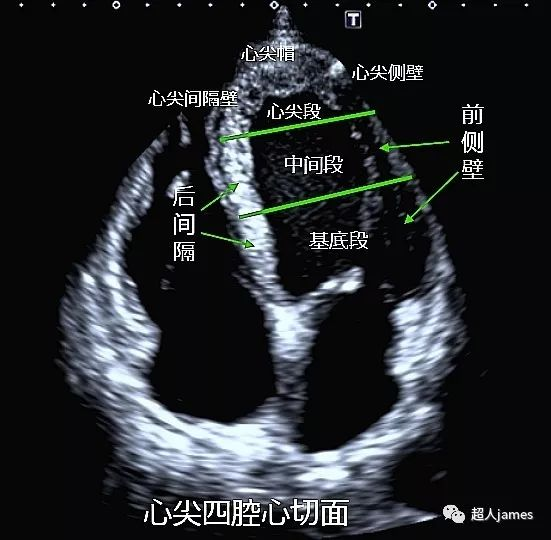

左心室分段图文全解

左心室对于会做心脏彩超的同行来说太熟悉不过了,但是对于大多数人来说真的了解了吗?今天我们主要来聊聊左心室的常用分段方法:

目前,左心室的分段主要有16节段、17节段和18节段几种分法,今天我们先看看16节段到底是怎么分的。